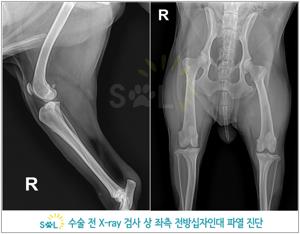

진단 방법

- 임상 증상과 이학적 검사(무릎의 불안정성 확인)

- 방사선(X-ray) 촬영

- 관절 초음파 검사 등 영상 진단